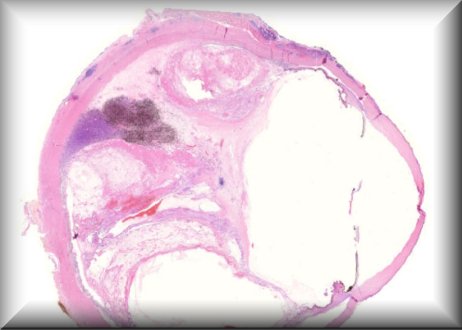

Karin Löffler: Enucleation of a painful blind eye after perforation injury 39 years ago (and multiple surgeries during the following years). |